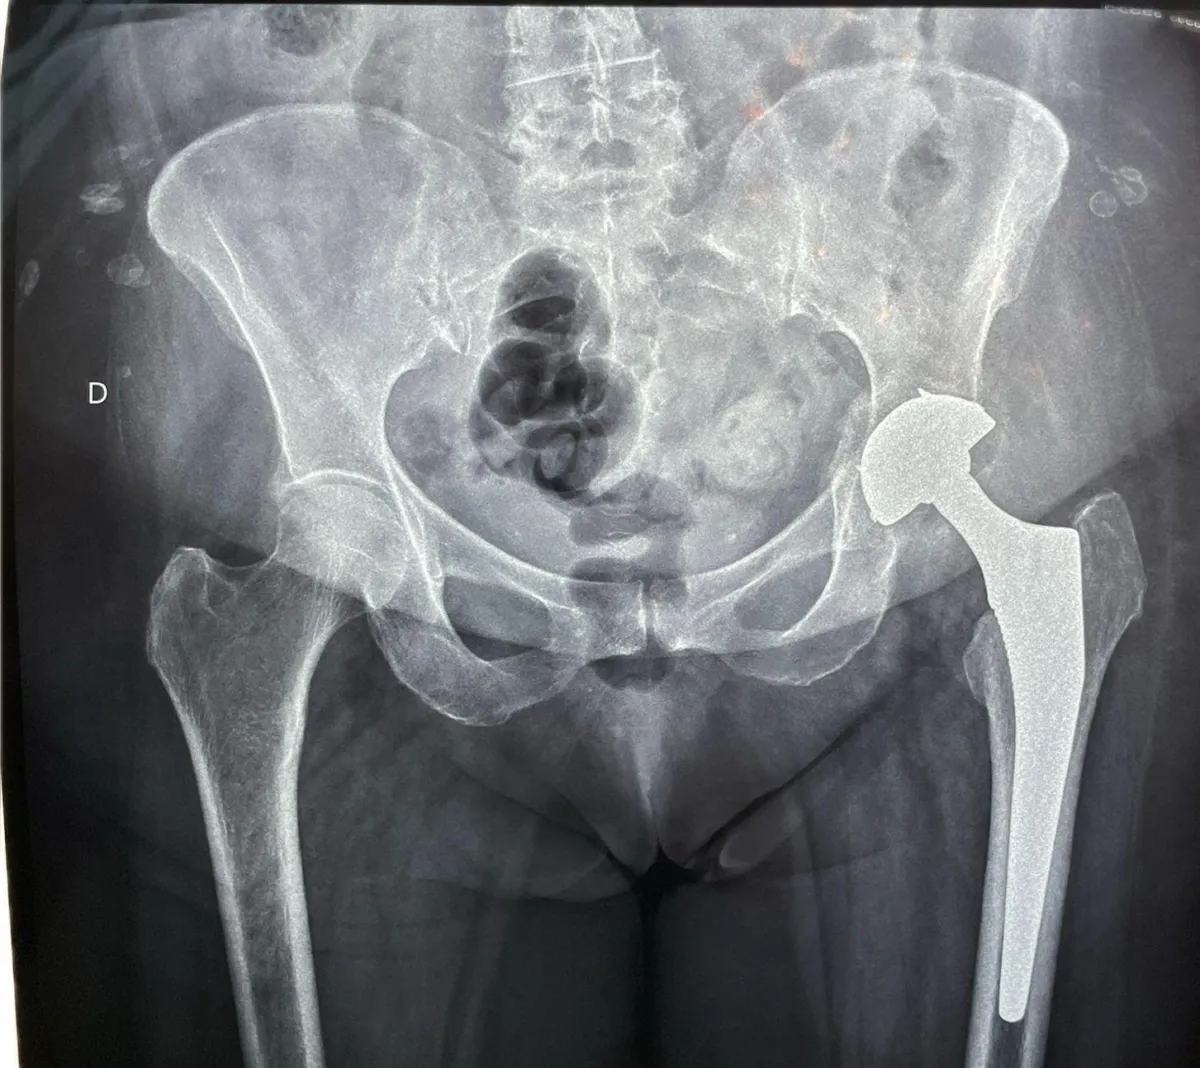

Prótesis de Cadera

Complicación manejada con prótesis de doble movilidad

Paciente al segundo día postoperatorio. Complicación abordada mediante colocación de prótesis de doble movilidad.